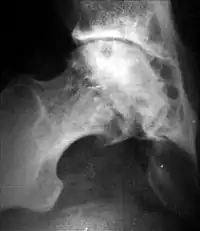

Кистовидная перестройка головки бедра и вертлужной впадины при диспластическом коксартрозе

Результатом поражения суставных хрящей являются очаговые дистрофические и некротические процессы в субхондральной губчатой кости, соответствующие локальным пикам механических напряжений. В результате этих процессов формируются кистовидные образования. Последние наиболее характерны для коксартроза, при котором они часто множественны и достигают больших размеров (эрозивный артроз).